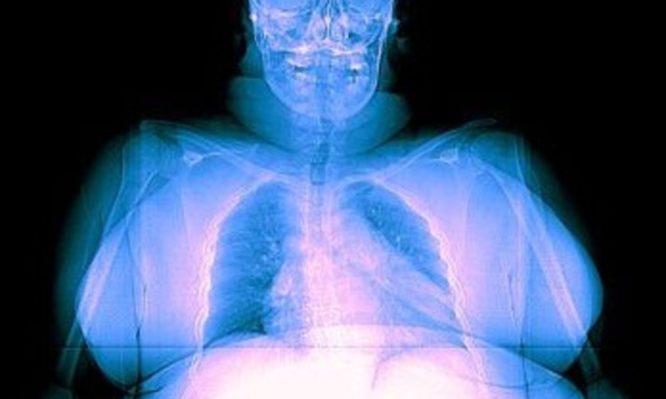

Οι παχύσαρκοι δέχονται περισσότερη ακτινοβολία στις ακτινογραφίες

Ερευνητές από το Πολυτεχνείο της Νέας Υόρκης, κατέληξαν σε αυτό το συμπέρασμα, ύστερα από εκτιμήσεις που έκαναν, με τη βοήθεια υπολογιστικών μοντέλων και προσομοιώσεων, σχετικά με την ακτινοβολία-Χ που απορροφούν οι ιστοί ενός οργανισμού ανάλογα με το βάρος του

Οι επιστήμονες κατέληξαν στο συμπέρασμα ότι οι ακτινογραφίες και τομογραφίες εκθέτουν τα εσωτερικά όργανα των παχύσαρκων ανδρών σε περίπου 62% περισσότερη ακτινοβολία, ενώ για τις παχύσαρκες γυναίκες η αντίστοιχη αύξηση της ακτινοβολίας είναι 59% κατά μέσο όρο.

Επειδή οι παχύσαρκοι άνθρωποι προσλαμβάνουν περισσότερη ακτινοβολία σε αυτές τις ιατρικές διαγνωστικές εξετάσεις, αντιμετωπίζουν κατά 60% μεγαλύτερο κίνδυνο εμφάνισης καρκίνου σε σχέση με ένα άνθρωπο μέσου βάρους. Όμως ο κίνδυνος σε απόλυτα νούμερα παραμένει χαμηλός, κατά τους ερευνητές, και δικαιολογείται από το διαγνωστικό όφελος.

Όσες περισσότερες απεικονιστικές διαγνωστικές εξετάσεις με χρήση ακτίνων-Χ κάνει κάποιος στη ζωή του, τόσο συσσωρεύεται ακτινοβολία στον οργανισμό του και αυξάνεται έτσι σιγά-σιγά ο κίνδυνος καρκίνου, αν και πάντα παραμένει μικρός σε απόλυτα νούμερα.

Η έρευνα επισημαίνει ότι τα μηχανήματα για τις ακτινογραφίες και τομογραφίες δεν είναι ρυθμισμένα κατάλληλα για τους παχύσαρκους, με συνέπεια, όταν αυτά λειτουργούν στη συνηθισμένη ισχύ τους, να προκύπτουν θολές εικόνες, καθώς τα φωτόνια των ακτίνων-Χ δυσκολεύονται να διαπεράσουν τα στρώματα λίπους των ανθρώπων με παραπανίσια κιλά. Έτσι, οι χειριστές των μηχανημάτων αναγκάζονται να ανεβάσουν την ισχύ για να πετύχουν καλύτερη εικόνα, όμως αυτό αυξάνει την έκθεση των παχύσαρκων ατόμων στην ακτινοβολία.